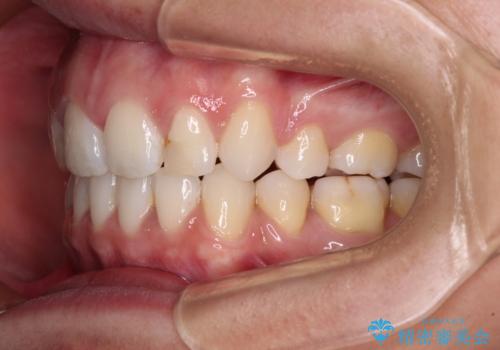

- くちばしのような前歯の突出感を気にして来院された患者様です。

上下左右第一小臼歯4本を抜歯して、積極的に口元を引っ込めるよう、ワイヤー装置にて矯正治療を行うこととしました。

抜歯矯正を行ったことで、顎先のつっぱり感や口元の閉じにくさを解消することができました。